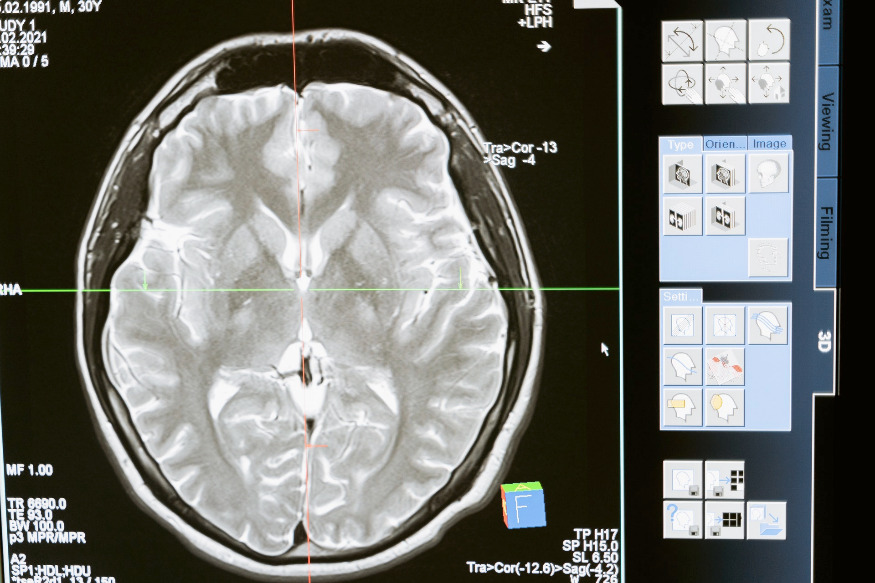

Le Dr Jean Lindsay, médecin généraliste, aborde dans Santé-vous bien le théme "Cerveaux en danger".